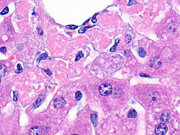

Microgranulomas consisting of mononuclear inflammatory cells and associated with hepatocyte necrosis are commonly seen in mouse liver.

Granuloma in the liver of a B6C3F1 mouse.